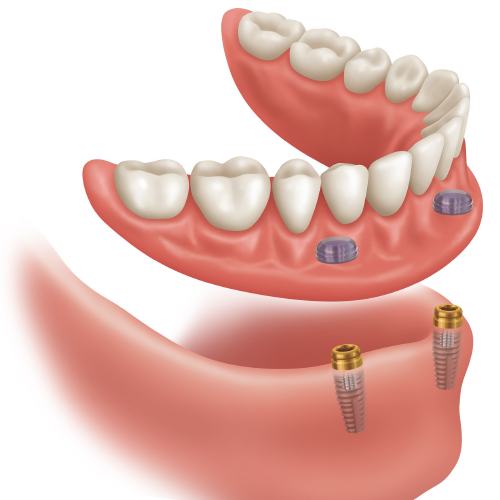

Grand Design: Implant and Full-Arch Solutions for Strength and Stability

Implant therapy has become an integral part of clinical dentistry, with ever-increasing numbers of patients seeking this treatment. However, this good news comes with a significant challenge: patients have increasing expectations for shortened treatment duration - even patients with anatomical deficiencies. You need serious treatment flexibility to create optimal outcomes for all indications. Learn more about advanced system options in this new eBook.

Locating Success in Retrofitting Overdentures

Direct retrofitting saves patients time and allows them to leave immediately with an attached prosthesis. In this eBook, three cases are presented, illustrating a few of the many circumstances that dentists who fit overdentures face every day. Don’t get stuck “chasing the pea around the plate.�...